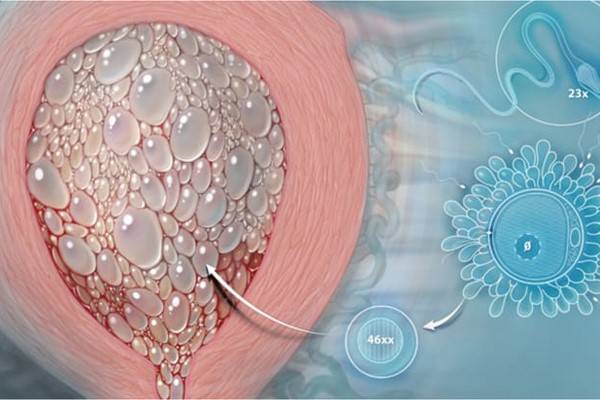

Thai kỳ bắt đầu khi trứng kết hợp với tinh trùng tạo thành phôi thai. Tế bào sẽ mang 46 cặp nhiễm sắc thể. Mỗi cặp sẽ chứa 2 nhiễm sắc thể : một từ mẹ, một từ cha. Thai trứng xuất hiện khi có sự bất thường trong quá trình thụ tinh, dẫn đến mất cân bằng trong thành phần nhiễm sắc thể.

Cụ thể, đây là hiện tượng nhau thai sản sinh quá mức, tạo ra sự phát triển của các khối không kiểm soát được, dẫn đến hình thành các nang trông như quả trứng hay chùm nho. Hiện tượng này có thể dẫn đến một số biến chứng nặng nề, thậm chí là ung thư nguyên bào nuôi. Vì thế, nó cần được phát hiện sớm để điều trị và theo dõi.

Hiện tượng chửa trứng bán phần có sự thụ tinh của một trứng và hai tinh trùng. Trường hợp này mặc dù có thông tin di truyền đầy đủ nhưng hợp tử phát triển không bình thường, tạo ra hiện tượng chửa trứng có phôi thai bất thường.

Hiện tượng thai trứng xuất hiện do những bất thường trong quá trình thụ tinh. Tế bào con bình thường chứa 23 cặp nhiễm sắc thể gồm một nhiễm sắc thể từ mẹ và một nhiễm sắc thể từ cha.

Tuy nhiên, trường hợp chửa trứng bán phần, nhiễm sắc thể của mẹ vẫn được bảo tồn xong của người cha có đến hai bộ nhiễm sắc thể. Kết quả là có đến 69 nhiễm sắc thể thay vì 46 như bình thường.